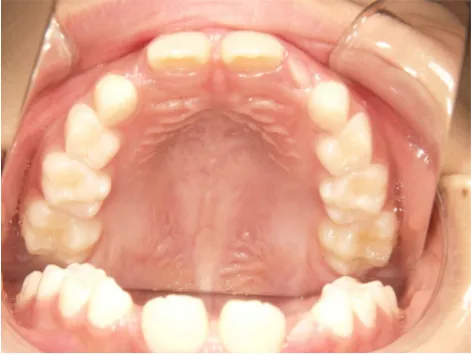

治療前①小2:8y1m 初診

治療スタート:8y2m QH・BHで拡大、前歯の並び替えスタート

| カウンセリング・診断結果 | 前歯が受け口になっていているため、適正な成長へ誘導するために前歯の咬み合わせの改善が必要なことを説明し、診断を希望されたので精密検査へ進みました。 精密検査の結果、骨格的には受け口傾向、下顎前歯の突出、上下ともアーチが小さく凸凹(叢生)が認められ、機能的には低位舌と口唇閉鎖不全があり、口元は上下唇とも突出していますがコンケーブになってないことがわかりました。 |